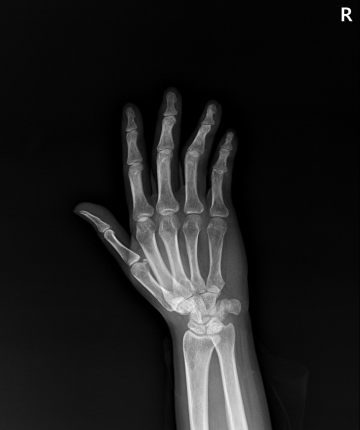

수술후

2023.01.04

ㆍ환자 동의를 받은 자료이며, 이미지 사진은 실물과 다를 수 있습니다.

ㆍ모든 자료는 새움병원 자료입니다.